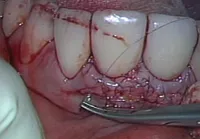

[使用例②]歯周病の外科的治療

![[使用例②]歯周病の外科的治療](/wp-content/uploads/unnamed.png.webp)

顕微鏡外科専用の道具を使用し、とても繊細な手術となる歯周病の外科的治療。

マイクロスコープを用いればより細かい作業も可能になるので、従来はできなかった部位の治療もできるようになりました。